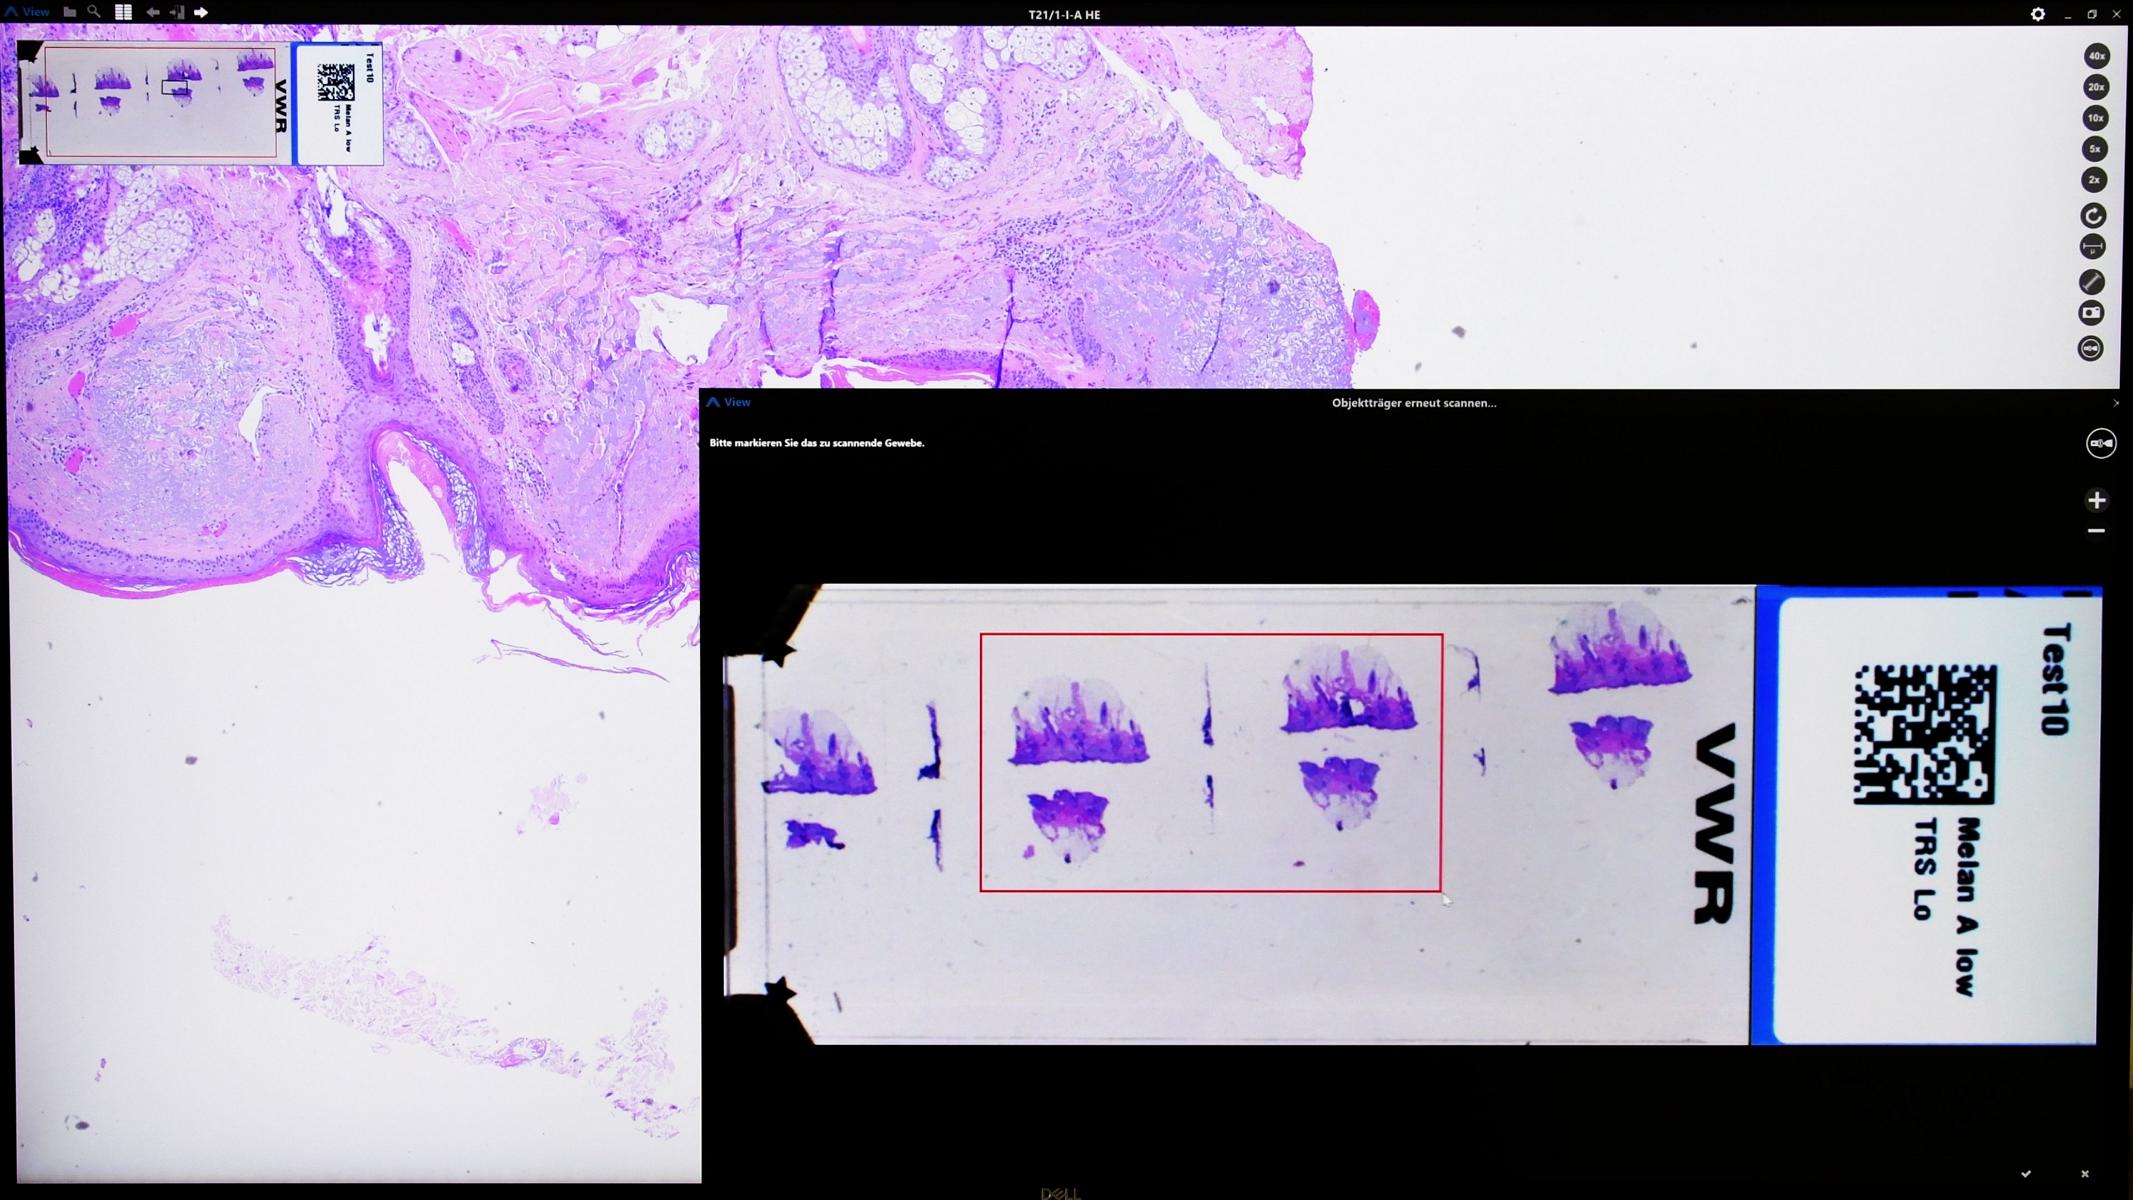

Der entscheidende Vorteil der ARGOS Technologie liegt in der RE-SCAN® Funktion. Damit hat der Pathologe während der Befundung einen direkten Einfluss auf die Bildwiedergabe, ohne das ein Objektträger die Anlage verlässt. Diese besondere Eigenschaft ist absolut einzigartig und ermöglicht einen erneuten Scanvorgang von am Monitor markiertem Gewebe bei Bedarf auch in 40x Auflösung ohne manuellen Eingriff.

Das Anstoßen eines weiteren optionalen Scans (RE-SCAN®) für höhere Detailaufnahmen ist über unsere Software problemlos möglich, da die betroffenen Objektträger für diesen Zweck in der Warteposition des ARGOS 6X bis zur vollständigen Versiegelung des Falles für weitere Scans vorgehalten werden.

Mit der integrierten RE-SCAN-Option können Bildbereiche definiert und der erneute Scan-Auftrag direkt aus dem Programm an den ARGOS 6X

übermittelt werden.